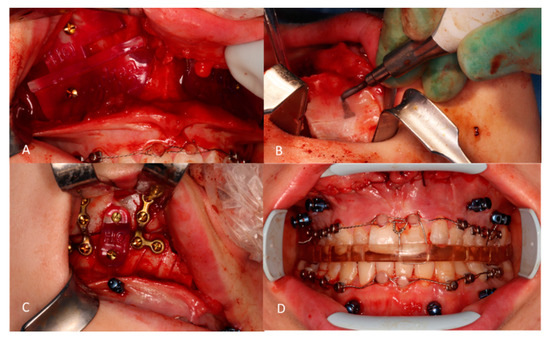

2.3. Le Fort 1 Osteotomy

2.4. Post-Operative Orthodontic Phase

| 1 week pre op | Buttons were placed on the planned teeth and fixated together with a steel ligature wire. |

| Surgery | Tads and corticotomies performed during the orthognathic surgical procedure. |

| 1 week post op | Buttons removed and patient instructed in using active aligners. |